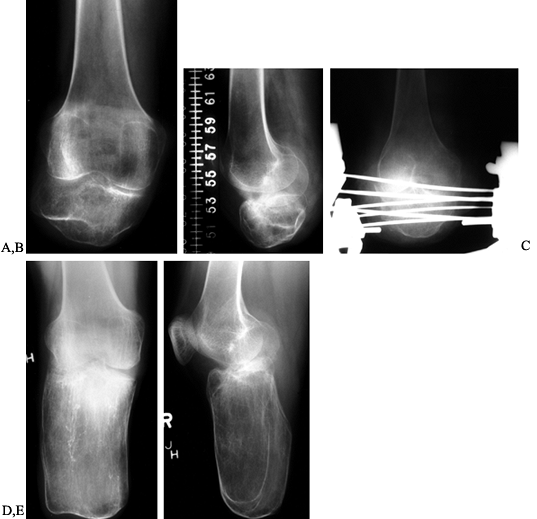

more distal than previously possible (Fig. 174.18).

![]() |

Figure 174.18. AP (A) and lateral (B) radiographs of a short, below-knee stump prior to lengthening. Lengthening in progress with an Ilizarov device (C). AP (D) and lateral (E)

radiographs showing the result of lengthening the stump. The patient was converted from a functional above-knee prosthesis to a below-knee prosthesis. |